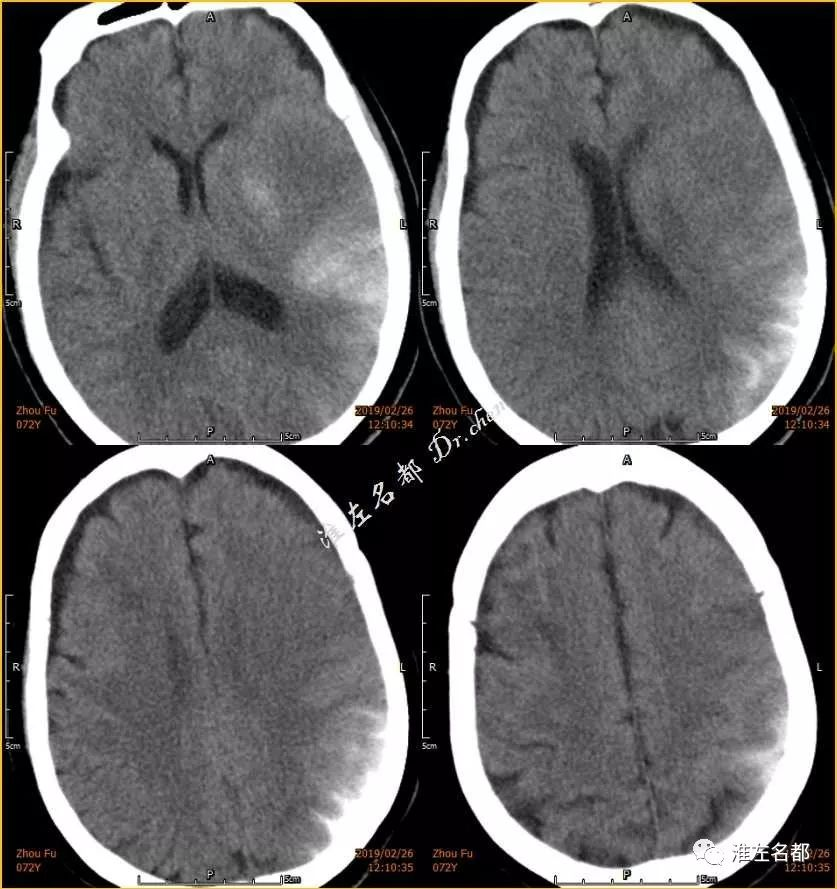

△术前CT:双侧半球均可见片状低密度影,右侧为亚急性梗死,左侧为急性梗死

△介入术后即刻CT:双侧半球可见多处高密度影,右侧为

亚急性梗死强化,左侧为急性梗死强化合并蛛网膜下腔出血

△介入术后第二日CT:右侧半球高密度消失,左侧半球基底节区少量出血高密度,蛛网膜下腔出血已有吸收